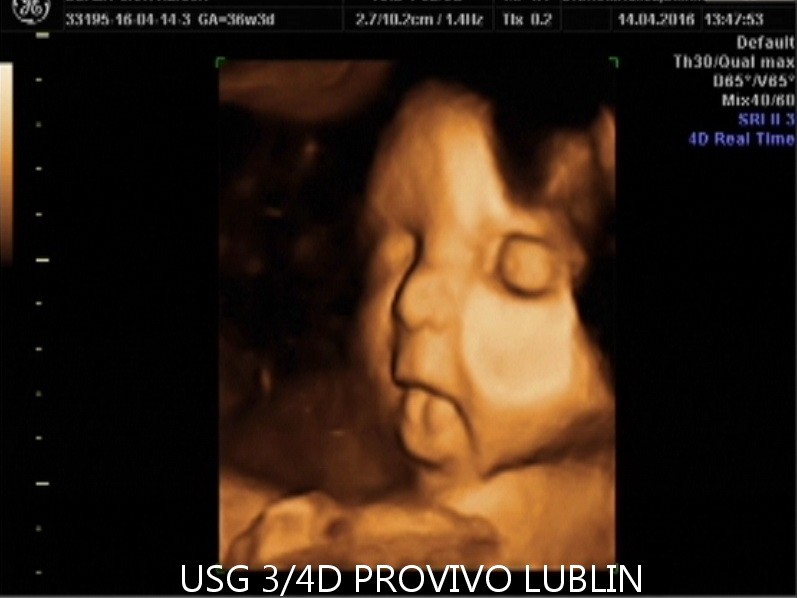

Badanie USG 3D/4D pozwala nie tylko na ocenę wybranych struktur i rozwoju ciąży, ale również na podgląd twarzy dziecka, jego ruchów oraz mimiki. To połączenie wartości diagnostycznej i wyjątkowego doświadczenia dla przyszłych rodziców.

Badanie USG 3D/4D w Lublinie umożliwia dokładny wgląd w rozwój płodu i pozwala zobaczyć dziecko w sposób zbliżony do jego aktualnego wyglądu. W porównaniu do klasycznego badania USG 2D obraz jest bardziej realistyczny i czytelny dla rodziców.

USG 3D daje możliwość trójwymiarowej rekonstrukcji obrazu płodu oraz wnętrza macicy. Dzięki temu można zobaczyć powierzchnię zewnętrzną ciała dziecka, a twarz płodu staje się znacznie wyraźniejsza niż w klasycznym badaniu 2D. To badanie szczególnie cenione przez rodziców, którzy chcą zobaczyć dziecko jeszcze przed porodem w bardziej realistyczny sposób. Na obecnej stronie PROVIVO wskazano również, że rodzice otrzymują zapis badania w formie elektronicznej.

USG 4D Lublin – obraz dziecka w czasie rzeczywistym

USG 4D pokazuje obraz podobny do badania 3D, ale dodatkowo rejestruje go w czasie rzeczywistym. Oznacza to, że rodzice mogą obserwować ruchy dziecka, mimikę twarzy i zachowanie płodu niemal jak podczas podglądu na żywo.